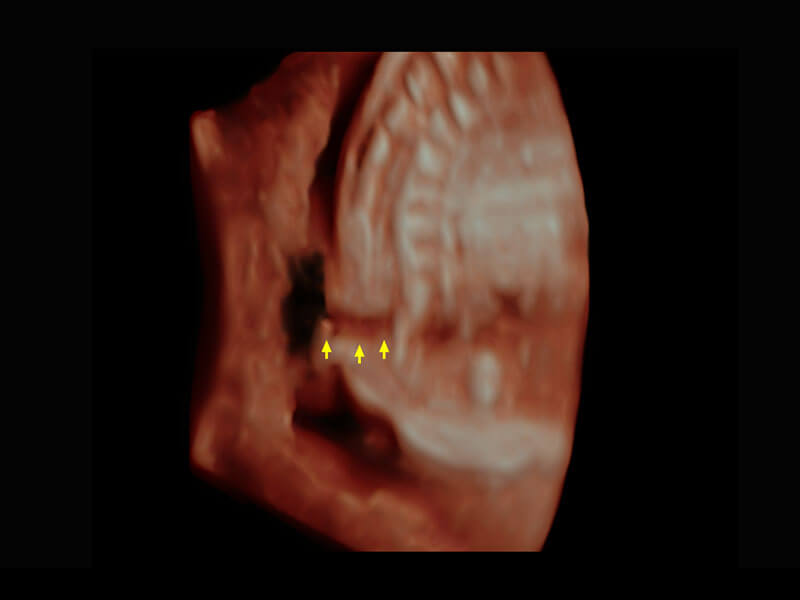

早孕-胎心

高分辨率容积成像-早孕胎儿

胎儿体循环

光影成像-孕囊